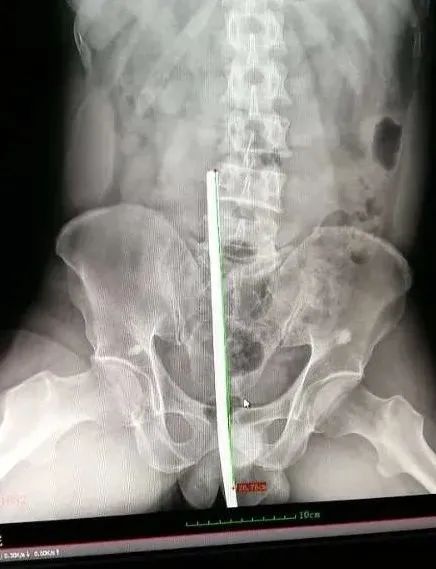

4月25日下午6时,惠东县人民医院普外科徐刚潮主任接到吉隆安康医院会诊病例,一名51岁男性患者,不慎摔倒,导致钢筋从会阴部插入体内,经腹部影像检查显示,钢筋约长35cm,考虑患者病情危急,需要多学科联合手术抢救,徐刚潮主任建议将患者立即送往我院进行手术,同时,将情况上报医院*党**委副书记、创伤救治中心组长杨必林,杨必林立即指示启动创伤急救应急预案,开通绿色通道,赶往现场指挥并组织普外科、急诊科、麻醉科、泌尿外科、骨科等救治专家制订周密的手术预案。

因情况紧急,手术按新冠肺炎疑似病例手术防护标准做准备,根据术前预案,由消化内科王捷鹏副主任医师行肠镜检查,随后,普外科徐刚潮主任医师团队上台开腹,探查见钢筋自会阴部插入盆底,贯穿后尿道,膀胱,直肠,直达腹膜后骶尾椎、腰4、5椎体旁,泌尿外科苏斌博士团队将会阴部切开,评估拔除风险后,骨科刘颗星副主任医师团队成功将约35cm的钢筋拔出,钢筋进入体内深度达约25cm。

徐刚潮主任医师团队完成术中腹腔止血,直肠破裂修补,乙状结肠造瘘。苏斌博士团队完成膀胱造瘘及尿道会师。病人术中出血1500ml,输血600ml,浓缩红细胞4单位。术后病人生命体征平稳,转入ICU进行单间隔离观察治疗。(截至发稿前获悉,病人核酸结果为阴性)